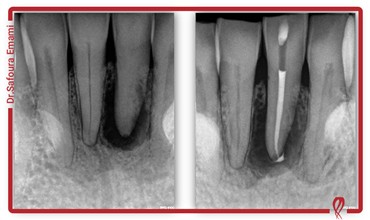

دکتر صفورا امامی متخصص درمان ریشه و عصب کشی

من صفورا امامی، متولد سال ١٣٥٩، متخصص درمان ریشه دندان و دارای رتبه دوم بورد تخصصی اندودانتيكس (درمان ریشه) در بین کلیه دانشكده هاي دندانپزشكی كشور در سال 1396 و در همان سال با عضویت در هـيأت علمی دانشگاه آزاد تهران مشغول به فعاليت شده و هم‎زمان مطب تخصصی خود را افتتاح كردم.